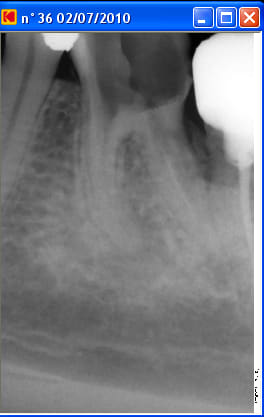

Un patient est venu pour la première fois en urgences pour douleur mandibulaire gauche: bilan radioclarté apicale sous la racine mésiale de 36, test percussion +++, ATB, disparition des douleurs à ce jour.

A la radio il y a une fausse route dans la racine mésiale.

Radiopreop1 reyqas - Eugenol